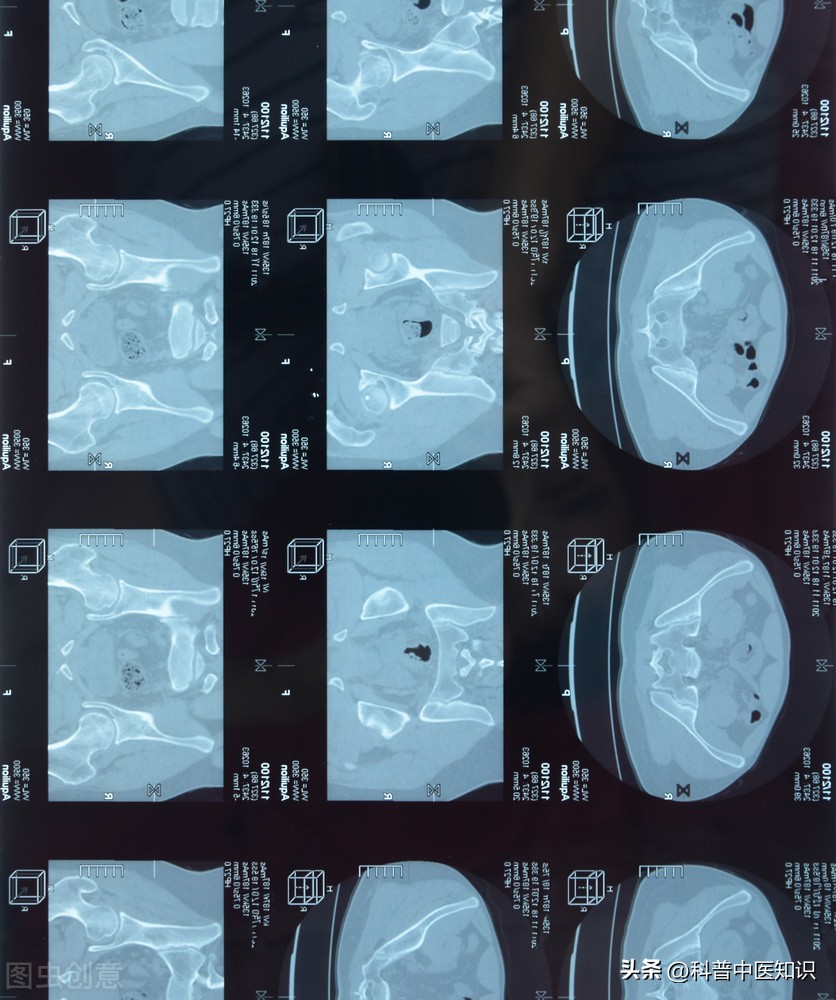

下面是著名中医焦树德教授的一则医案:一男20岁,患者半年前自觉腰髋部及双膝关节疼痛,遇热则痛减,伴僵直不舒。曾于当地医院查血沉70mm/h。予以青霉素、链霉素和炎痛喜康片等治疗无效。近日来腰髋关节痛加重,坐时尤著,腰椎僵直感明显,前弯、侧弯、后仰活动受限,双下肢无力,不能下床活动,生活不能自理。遂收入院治疗。入院后查血沉45mm/h,类风湿因子(-)。腰骶椎正侧位片示:两侧骶髂关节改变符合强直性脊柱炎。查体:腰椎旁压痛(+),腰背肌肉呈板状僵硬,双下肢肌肉萎缩,不能下地行走。舌质淡,舌苔白,脉细滑,诊断为强直性脊柱炎。

强直性脊柱炎过去被认为是类风湿关节炎的一个临床类型。后来发现,HLA-B27阳性的人群易患此病,证明了本病是一个独立的疾病。本病起病迟缓,以持续性腰或涉及胸、颈段脊柱疼痛,晨僵,活动受限,甚则出现驼背、脊柱强直、骶髂关节受损,两腿活动受限等,为主要症状的疾病。强直性脊柱炎的发病男性多于女性,且易多见于15—40岁左右的青少年及中年人。实验室检查90%以上的患者HLA—B27阳性。X线拍片显示:骶髂关节融合。对强直性脊柱炎的治疗,焦树德教授有自己独特的见解。